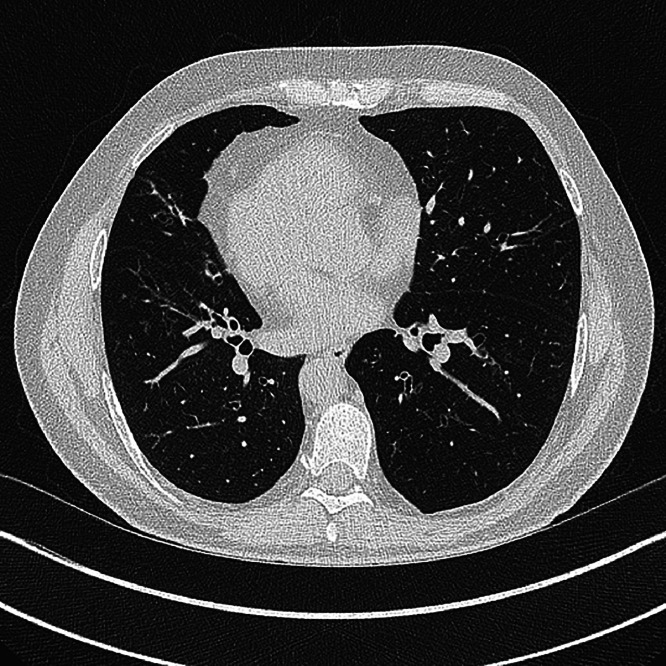

Abstract Image